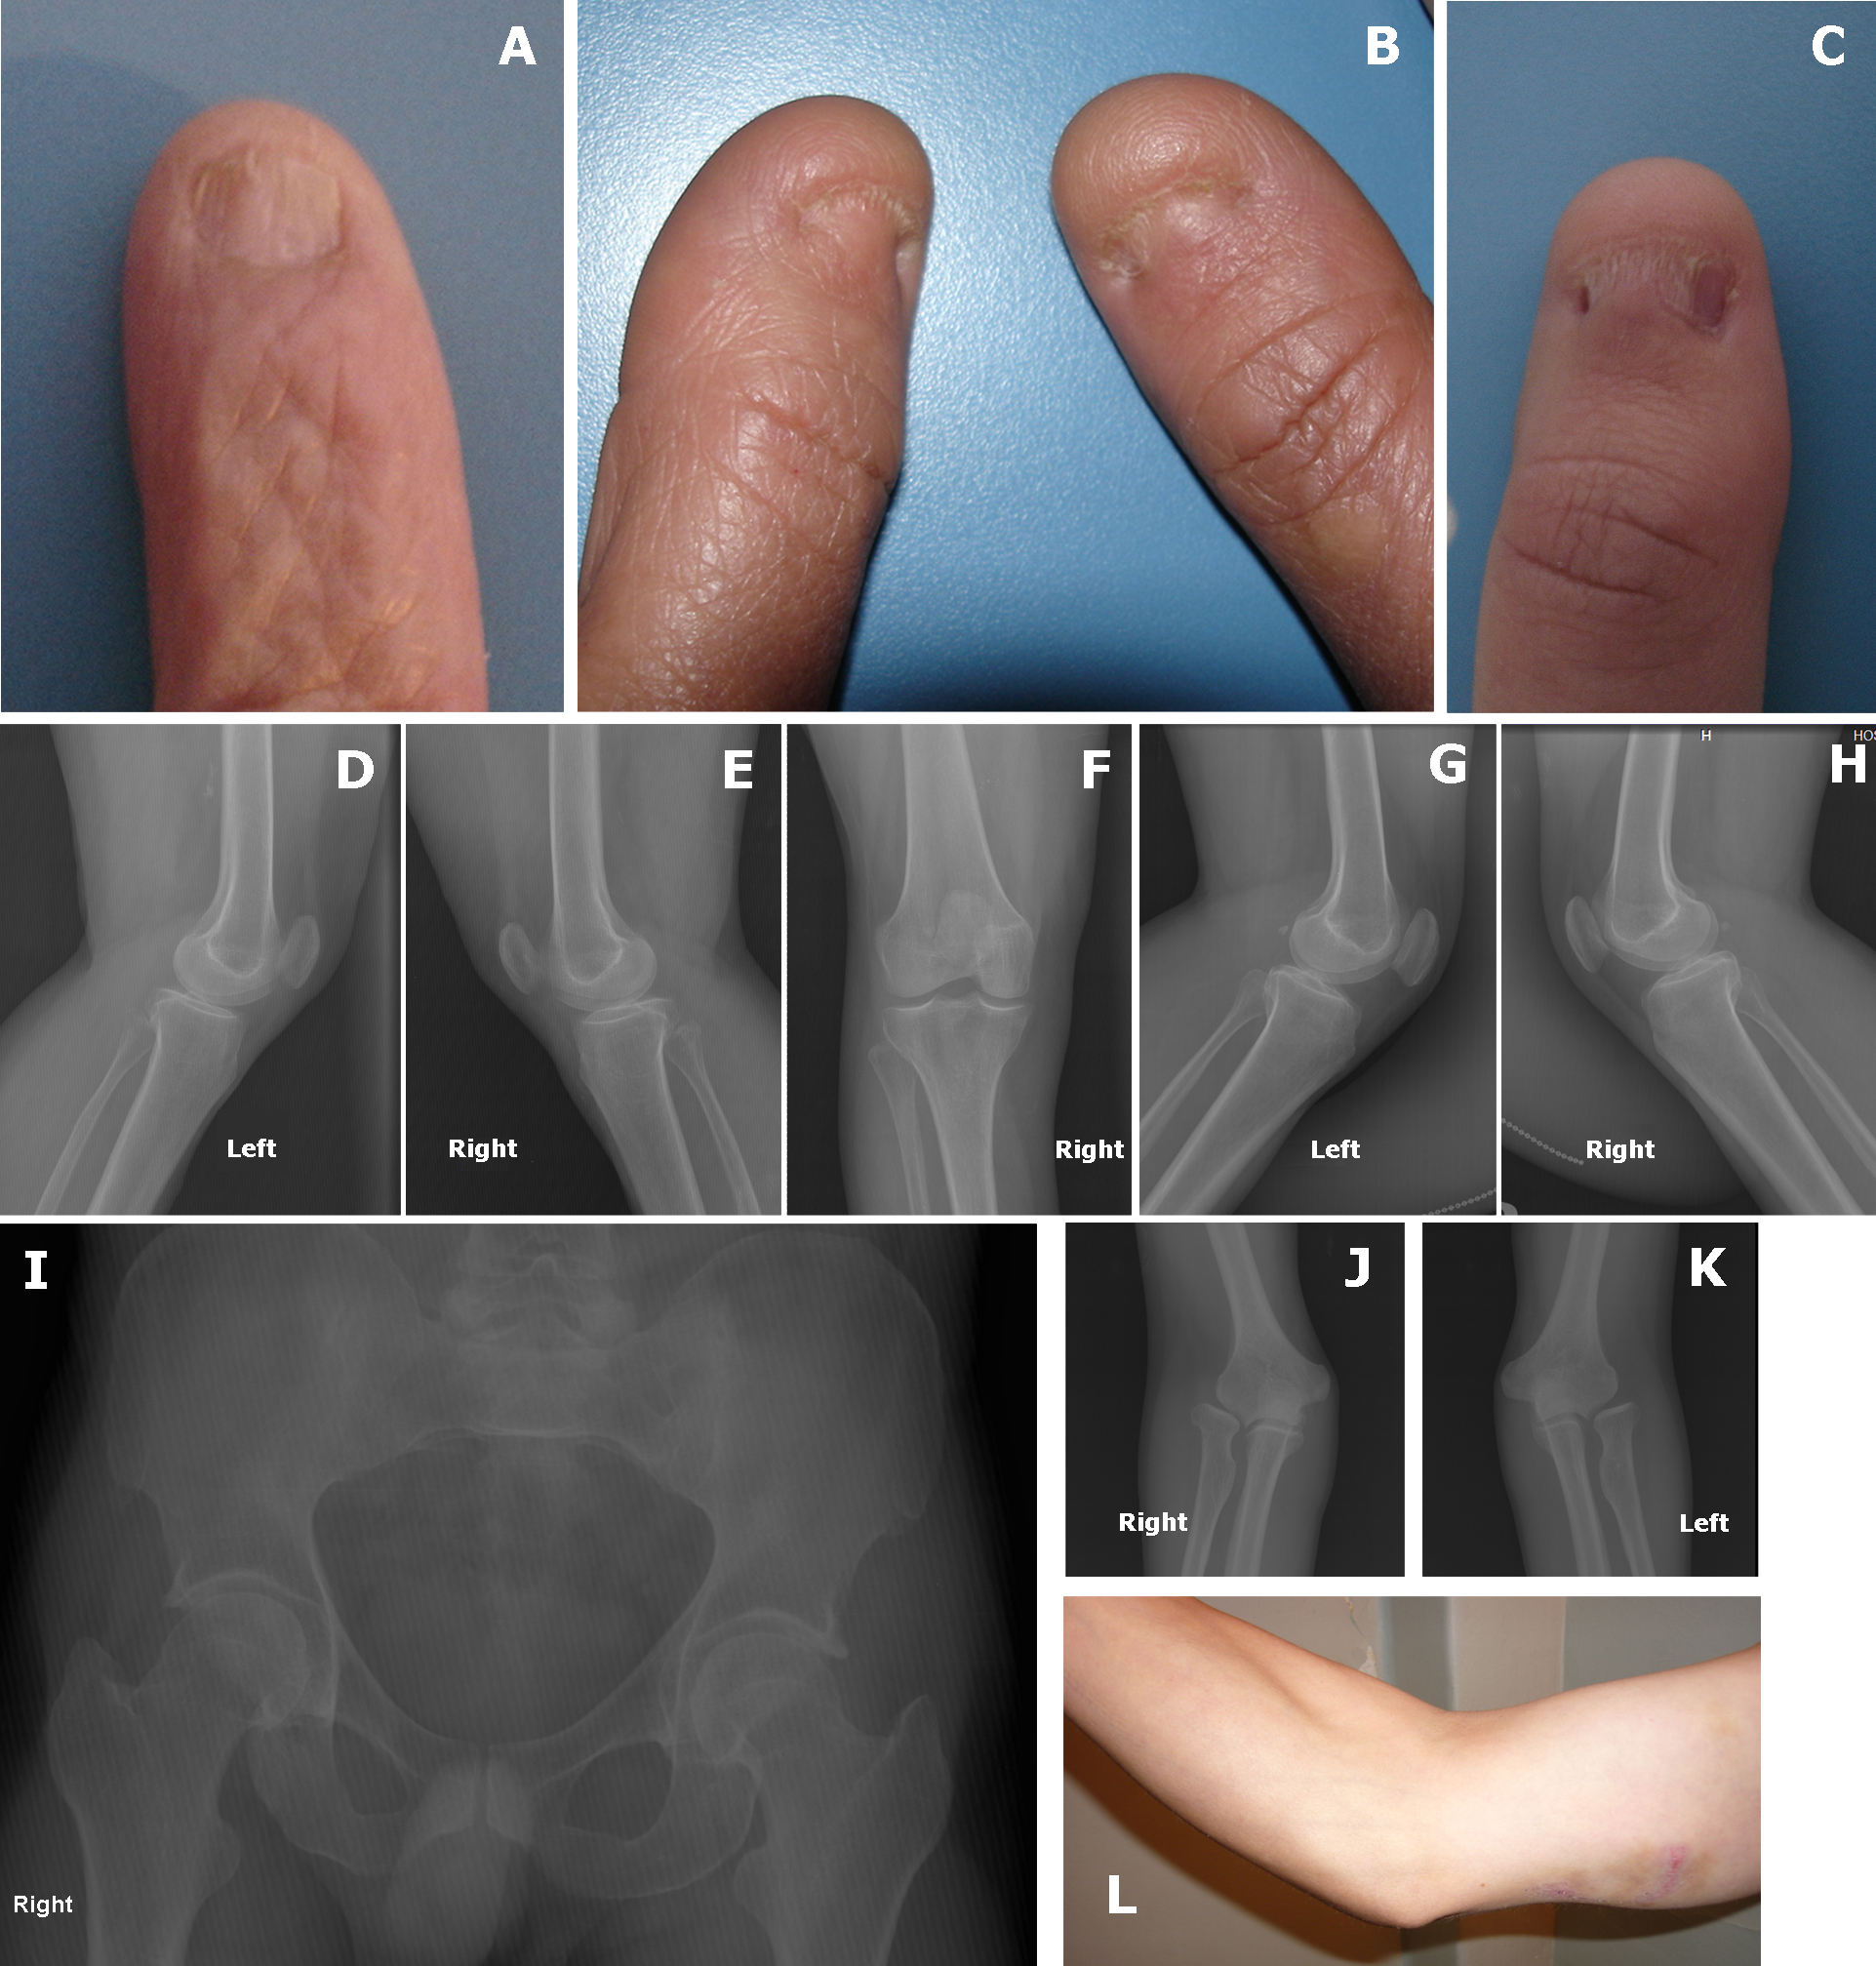

Figure 5. Photographs of the nails and

radiographs of knees, hips and elbows of some of the subjects. Nail

involvement in these cases includes dystrophic, thin, hypoplastic

discolored nails with longitudinal ridges. Case III-2 shows decreased

creases over the skin of distal interphalangeal joints, which is a

sensitive sign of digital involvement in this patient (A).

Thumbs are most severly affected in case III-7 (B), and IV-9 (C).

The

radiographs of knee involvement in Case III-2 shows bilateral

involvement of the patella, with hypoplastic, higher than normal

missplaced patella (D-F). A small 6 mm bone fragment can

be observed on the lateral border of right patella (E). Knee

radiographs of Case III-7 show slight bilateral patellar hypoplasia,

mostly on the transverse diameter (G and H). Hip

radiography of Case IV-2 shows loss of the normal concavity at the

junction between the head and femoral neck bilaterally. The radiographs

reveal an elbow involvement of subject IV-2 (J and K)

and include a prominent medial epicondyle and hypoplasia of the

capitellum on both sides (J and K). They also show a

hypoplasia of the lateral epicondyle and capitellum with a slight

deformity of the radial head (J and K). Underdeveloped

triceps and prominent medial epicondyle are observed (L).